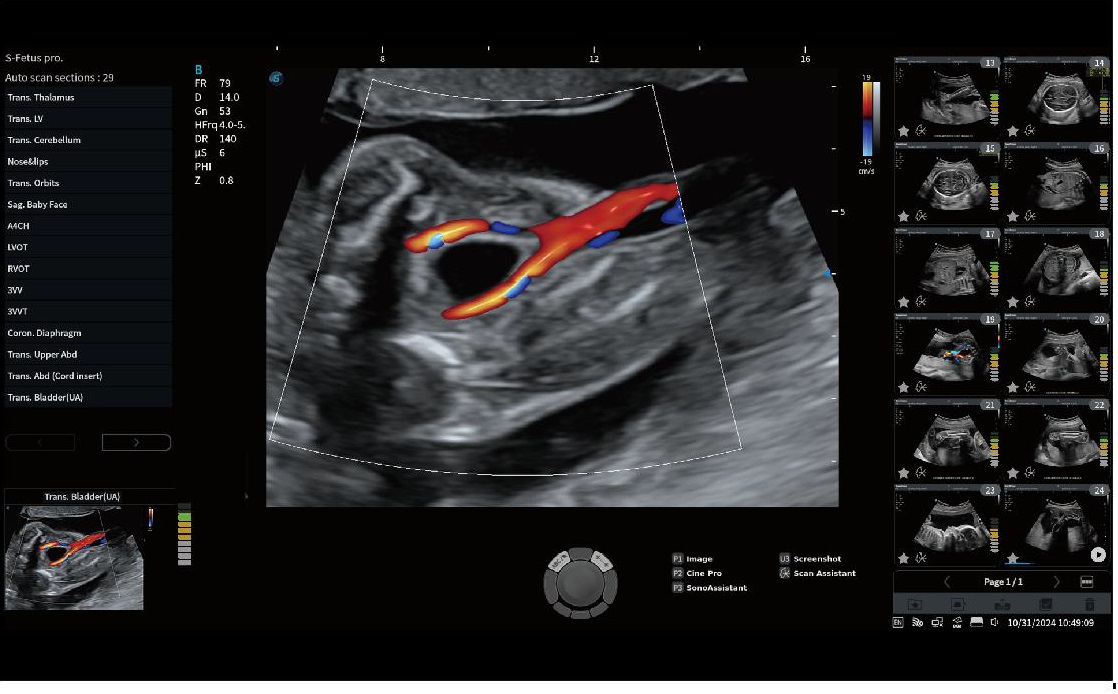

S FETUS

S-Fetüs Obstetrik Ultrason İş Akışını Otomatikleştirir S-Fetus, standart obstetrik ultrason prosedürünü basitleştiren bir fonksiyondur. %80 daha az tuş vuruşu %90 daha az zaman %95'ten fazla doğruluk

STIC

Zamansal ve mekânsal boyutlar boyunca frame ratelerin ortalamasını alarak, STIC farklı düzlemlerde görüntüler oluşturur; böylece hızla hareket eden fetal kalp yapılarını farklı açılardan kapsamlı bir şekilde inceleme ve değerlendirme olanağı sağlar.